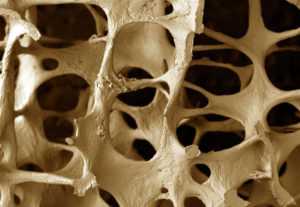

Костная ткань даже в здоровом состоянии представляет собой пористую структуру, но при остеопорозе ткани костей становятся слишком рыхлым. Перелом кости, имеющей дефектную структуру, является большой проблемой, так как восстановить функциональность кости в дальнейшем очень проблематично. Все дело в том, что костная ткань в этом случае очень плохо срастается. Несмотря на то что существует большое количество методик лечения остеопороза, редко когда удается полностью восстановить костные структуры. Проблема заключается не только в самых имениях структуры костей, но и в старческих изменениях метаболизма.

Разрушение костной ткани — физиологический процесс, как и минерализация. В норме наблюдается их баланс.

Данные процессы обеспечиваются слаженной работой остеобластов и остеокластов.

В основе развития остеопороза лежит недостаточная минерализация или усиление процесса разрушения тканей.